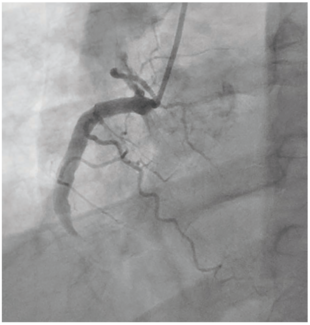

John A. Phillips, MD, FACC, FSCAI, RPVI; Jessica Pickard, BS, MS-IV; Adam Reitz, DO

This case report aims to shed light on the potential utilization of renal artery stents within aneurysmal coronary vessels to provide patients with ACAD first-line intervention in the setting of acute coronary syndrome.